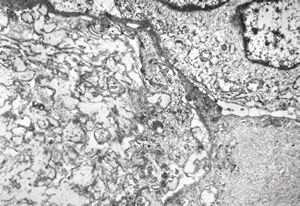

oral saprophytic bacterium